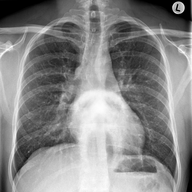

Scan Results: Leo Alvi

Scan results that are accompanied by a note from Dr. Auchee

Mr Alvi, I regret to inform you that I have not made much progress in interpreting the scan results. The image is still very corrupted. I have ran numerous diagnostics on the equipment and everything seems to be in working order leaving me to believe that it was subject to some sort of interference. At this point, we are out of the realm of general medicine and may need to look for expert consult. However, I'm at a loss as to the specialty.

I have attached a copy of the scan, shall you find yourself able to contact a specialist.